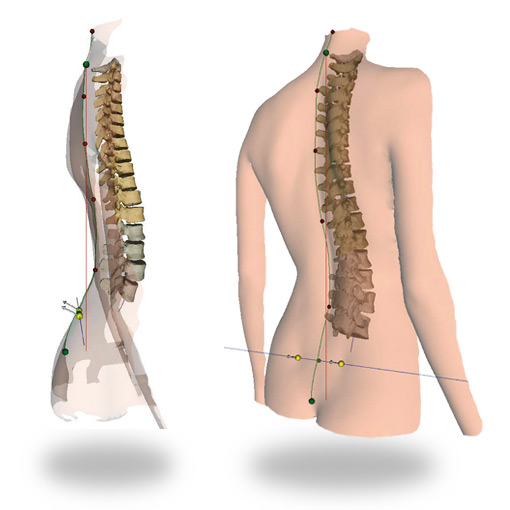

Оптическая диагностика позвоночника Diers: изображения и технологии